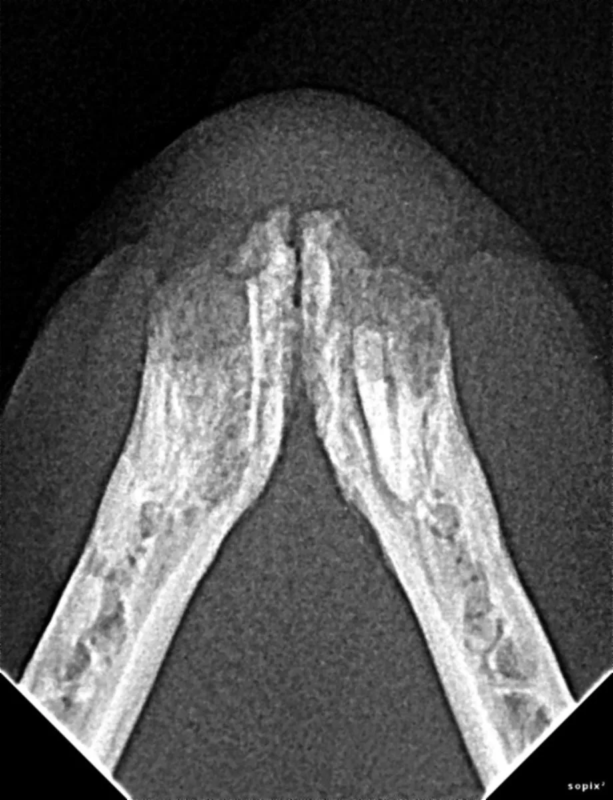

Tooth Resorption

Tooth resorption is a disease process where the body begins to break down the adult tooth. It is widely known to occur in cats but can also occur in dogs. In cats these lesions are thought to be inflammatory, while in dogs they can be more of a replacement resorption process. These lesions can be very painful and should be treated, generally with extraction depending on the type of resorption that is occurring. The disease can be progressive and affect many teeth over several years. It is important to have regular checkups and yearly dental cleanings to monitor for these lesions.